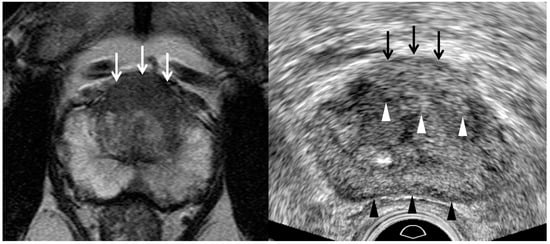

| Tumor Location/Morphology | MRI | TRUS |

|---|---|---|

| Scan axis to urethra | Perpendicular | Oblique |

| Anterior 1/3 location | Base and mid-gland | Mid-gland and apex |

| Middle 1/3 location | Same location | Same location |

| Posterior 1/3 location | Apex and mid-gland | Mid-gland and base |

| Tumor size | Different size | Different size |

| Tumor shape | Different shape | Different shape |